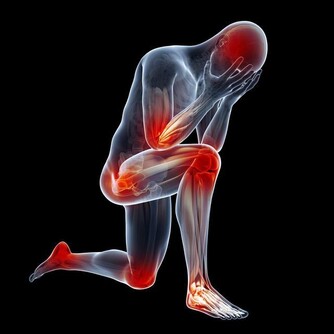

(7)皮膚發黑變粗:骨癌

這是骨癌的信號,不少胃癌患者在未發現任何症狀時,其腋下、肚臍周圍和大腿內側的皮膚會變黑變粗;有的患者面容和掌心皮膚也略呈黑色。